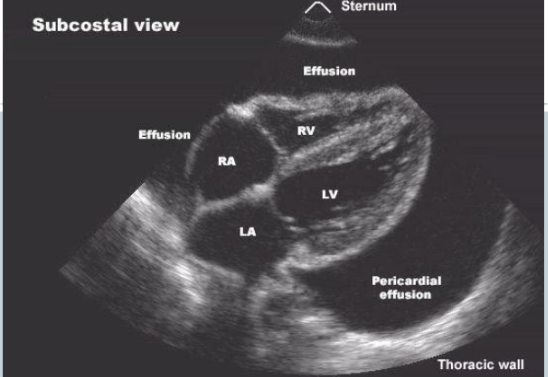

Pericardite Efusiva

• Derrame tende a acumular posteriormente no ecocardiograma

Tamponamento Cardíaco

• Quantidade não define gravidade mas sim velocidade do derrame

✓ Aumento da PVC,

✓ Bradicardia,

✓ Hipotensão arterial,

✓ Pulso paradoxal.

✓ Pode haver atrito pericárdico,

✓ Compressão do AD

✓ Colapso diastólico do VD.

✓ Dilatação da VCI

✓ Mais específico / menos freqüente ‘swinging heart’(pendular)